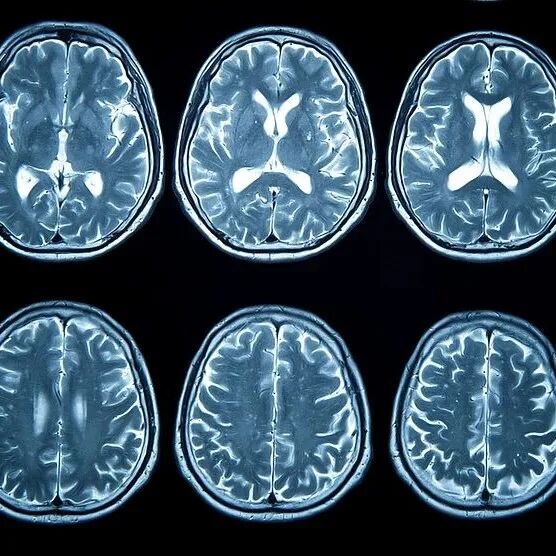

腦梗又稱“缺血性腦卒中”,是由于腦血管阻塞,導致腦部血液循環障礙,缺血缺氧引起的局部腦組織缺血性壞死。發病時,患者可表現為語言障礙、肢體麻木、視物異常及頭暈頭痛等。 臨床數據顯示,大多腦梗發生在后半夜。因為此時人體血液黏稠度最高,且人在睡眠狀態下血流速度較慢。如果存在動脈粥樣硬化疾病或者血管狹窄,就容易導致腦血管堵塞,引發腦梗。睡前若出現下列癥狀,就要當心了: · 進行性頭暈、頭痛。睡前出現進行性發展的頭暈、頭痛癥狀,且比平時更劇烈,看東西天旋地轉,這可能是腦組織缺血引發血管痙攣所致。 ·?身體一側發麻。腦梗后,由于一側頭部神經受壓迫,身體一側會突然發麻不適,伴有言語不清的表現。 ·?視物不清。睡前突然兩眼發黑、視物不清,休息后仍無法緩解,這可能是因頸內動脈眼動脈段供血不足,引發視網膜缺血。 ·?頻繁打哈欠。睡前頻繁打哈欠,伴隨全身無力、嗜睡、明顯頭暈等癥狀,需警惕腦部嚴重缺氧。 ·?經常流口水。睡覺時流口水,同時伴有嗜睡、頭痛或嘴眼歪斜等癥狀,這可能是局部腦組織缺血所致。